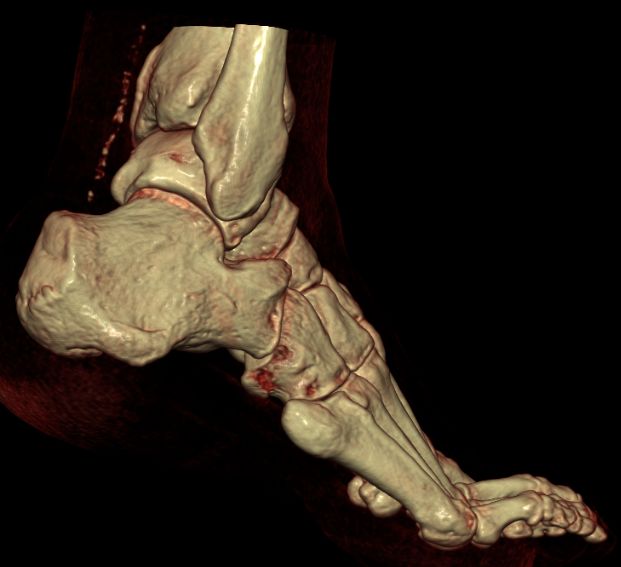

Metatarsalia (5)

Ossa Tarsi: Os cuneiforme (I-III), Os cuboideum, Os naviculare, Talus, Calcaneus

- Articulatio interphalangea distales

- Articulatio interphalangea proximales

- Articulatio metatarsophalangeae

- Articulatio intermetatarsales

- Articulatio tarsometatarsales

- Articulatio cuneocuboidea

- Articulatio intercuneiformes

- Articulatio cuneonaviculares

- Articulatio tarsi transversa

- Articulatio talonavicularis

- Articulatio calcaneocuboidea

- Articulatio talocalcaneonavicularis

- Articulatio subtalaris

- Articulatio talocruralis